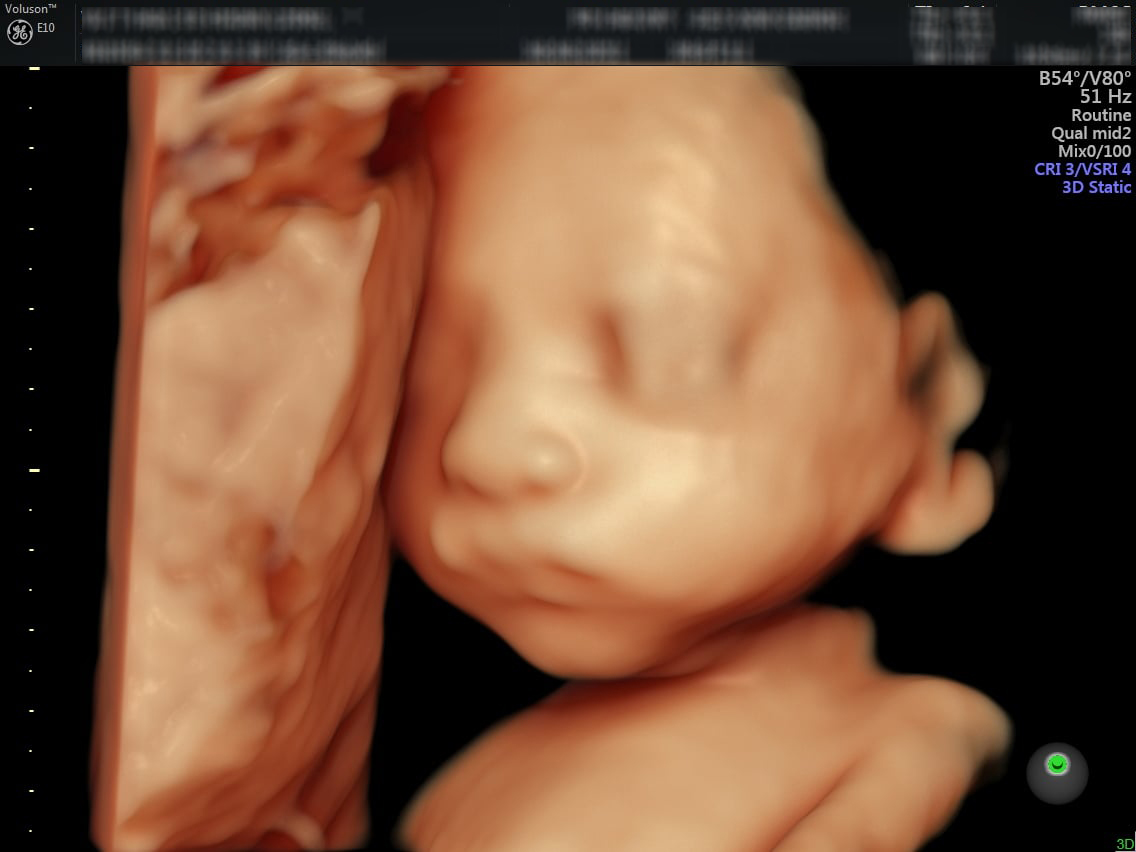

Siêu âm 4D, 5D

Siêu âm màu 4D, 5D giúp mẹ bầu 22 tuần quan sát hình thái học của thai nhi rõ hơn. Mẹ có thể thấy được mắt, môi, da, cột sống, nội tạng và dây rốn của con. Ngoài ra, còn biết nhau thai, âm đạo, tử cung và cổ tử cung của người mẹ có vấn đề gì hay không.